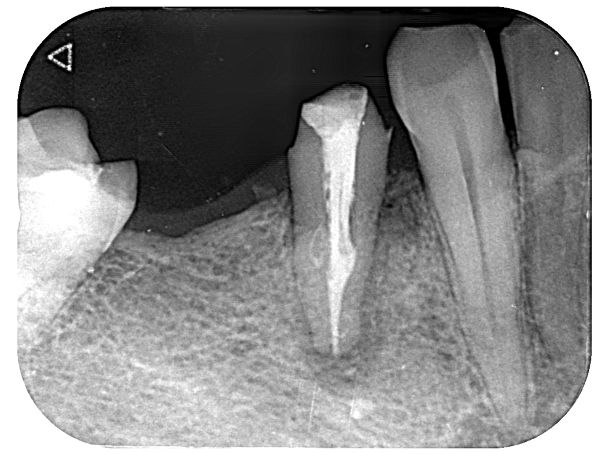

歯根破折は日本人の歯を失う原因の第3位(約18%)となっております。下記は歯根破折の症例の画像です。

やはり右下4番目の神経が取られている歯が歯根破折を起こし、抜歯となってしまいました。神経が取られている歯はブリッジの土台のみならず、単独でも歯根破折を起こすケースが多々あります。

このように弱っている歯にさらに負担をかけてしまうと、歯根破折を起こす可能性がかなり高くなってしまうのが分かるかと思います。